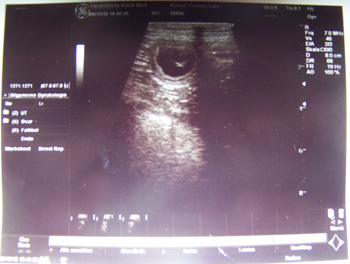

09.12.2015 Klitzekleine Naturgewalten- ein erster Blick auf die N-iños So ist das also bei Wurf Nummer 13, ich bin immer noch nicht viel geduldiger als beim ersten Wurf damals. Also habe ich den Ultraschall nochmal zwei Tage vorgezogen und bin nun froh, dass ich verkünden kann, dass wir den N-Wurf freudig erwarten können. Ca 3-4 kleine N-Zwerge haben wir gesehen, und so rechne ich mit einem durchschnittlich großen Wurf Mini Springer Mitte Januar.

|